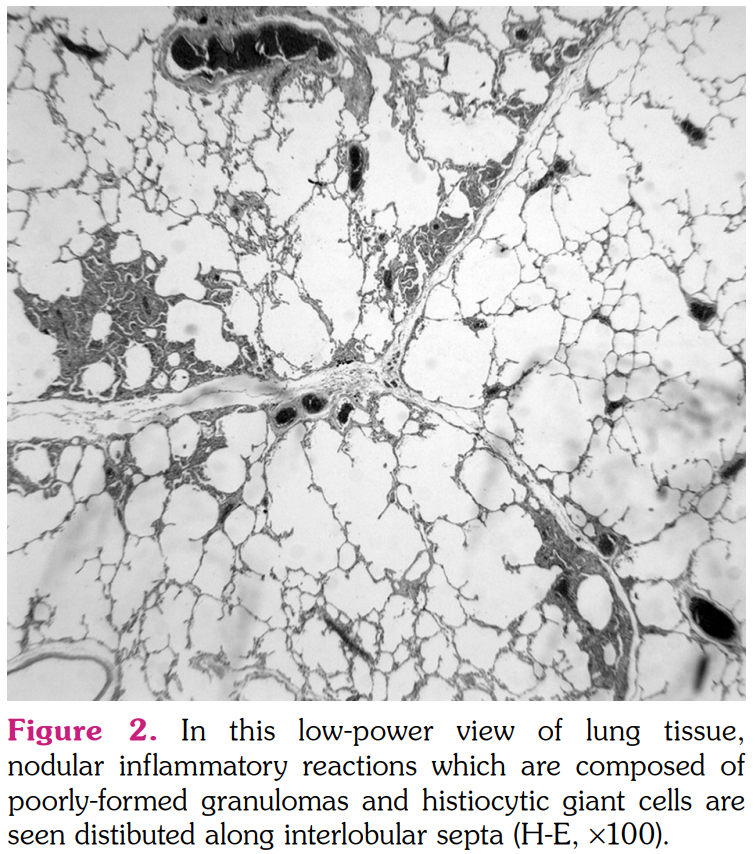

The smears of bronchoalveolar lavage (BAL) were negative for any bacteria, fungi, or acid- fast bacilli. Cytological examination revealed numerous macrophages, few lymphocytes, and few neutrophils. BAL cultures were also negative. Serological tests for the infection of viruses and fungi were negative. The pathological examination of pulmonary wedge resection performed from lingula revealed foreign-body type giant cell reaction and poorly- formed non-caseating granulomas distributed mainly along interlobular septa and subpleural zones (Figure 2). Asteroid bodies as well as a birefringent material were seen in the cytoplasms of giant-cell histiocytes under polarized microscope (Figure 3a, b). Histochemical stains did not reveal any microorganisms and lung tissue cultures were also negative for any mycobacteria species. Based on the clinical, radiological, and pathological findings, a diagnosis of sarcoid-like granulomatous reaction induced by adalimumab was confirmed. Given the lack of radiological response four months after cessation of adalimumab, methylprednisolone 32 mg/day peroral was initiated. The patient was controlled every month initially and every two months thereafter with a gradual reduction in methylprednisolone dosage. At the end of nine months of steroid therapy, a control CT of thorax revealed stable nodular opacities in both lungs. As psoriatic lesions gradually increased and worsened during this period, ustekinumab was started.